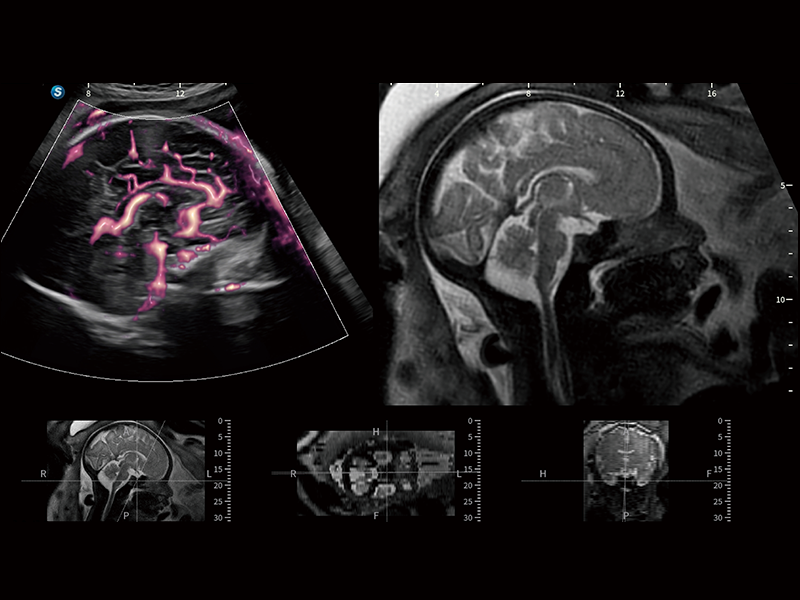

豐富的血流動(dòng)力學(xué)檢測(cè)技術(shù),可在不同醫(yī)療場(chǎng)景中高效捕捉血流信號(hào),助力臨床診療。

在傳統(tǒng)血流的基礎(chǔ)上優(yōu)化掃查和算法策略,能夠更好的抑制組織信息,提煉紅細(xì)胞運(yùn)動(dòng)信息,得到更高幀頻,高靈敏度和分辨率的血流信號(hào),還原更真實(shí)的血流動(dòng)力學(xué)。

通過(guò)光照模型,使二維血流顯示出立體的效果,增加血流的敏感性、成束性,減少外溢。可以和其他不同的血流技術(shù)聯(lián)合使用,融合不同技術(shù)的優(yōu)勢(shì)。輕松應(yīng)對(duì)微小血管,增強(qiáng)血流的立體效果,提升視覺(jué)敏感性。

通過(guò)創(chuàng)新的Matrix E自適應(yīng)濾波算法,能有效濾除軟組織和噪聲信號(hào),最大限度保留超低速微細(xì)血流的信號(hào);結(jié)合超長(zhǎng)時(shí)間域算法,極大提升細(xì)微血流的敏感性和空間分辨率,更真實(shí)的反應(yīng)組織、包塊的血流灌注情況。